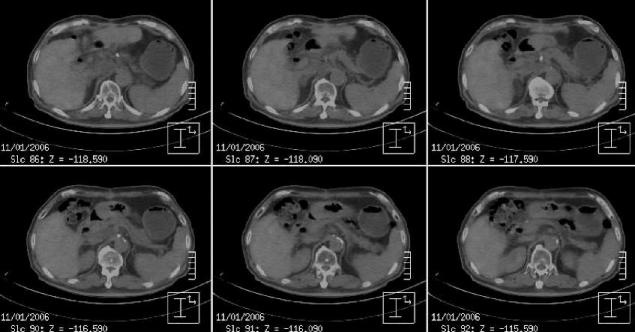

Fig. 3. 18F-fluorodeoxyglucose (FDG) PET/CT scan at 3.5 months after radiotherapy. The increased 18F-FDG uptake on the enlarged node was near completely disappeared.

The response of radiotherapy was remarkable and on 18F-FDG PET/CT scan, there was no increased FDG uptake on the metastatic node at 3.5 month from the end of radiotherapy (Fig. 3) and on abdomen CT scan, it was completely disappeared at 12 months from radiotherapy. There was no evidence of recurrence until 3.5 years follow-up (Fig. 4).